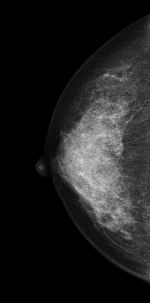

右CC画像 |

右トモシンセシス画像 |